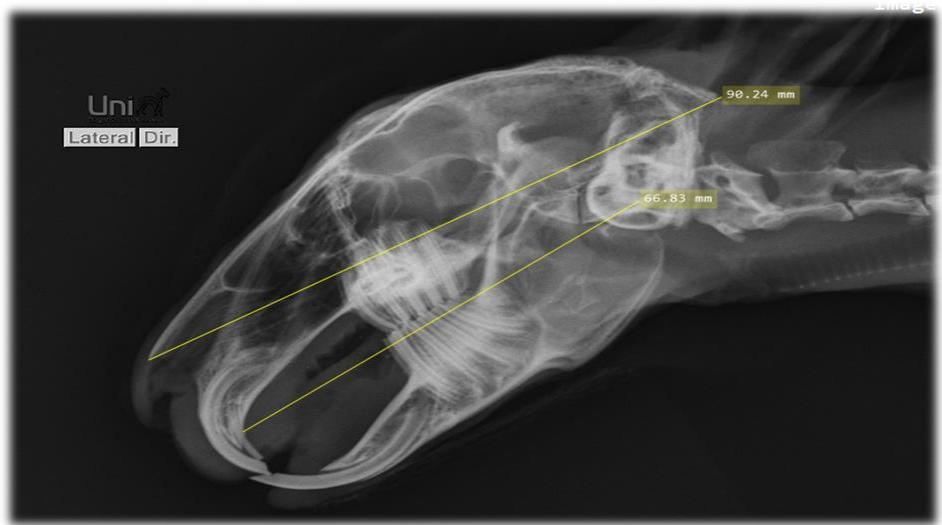

O exame da cavidade oral de roedores e coelhos domésticos faz parte de todo exame físico e é muito importante para o diagnóstico da síndrome do desgaste dentário inadequado, que leva ao hipercrescimento dentário e consequentemente a problemas sistêmicos, no entanto, o exame oral em um animal consciente fornecerá apenas informações limitadas. O exame oral definitivo só pode ser realizado sob anestesia geral SOARES, Helena Baggio (2018). Tem havido inúmeras publicações nas últimas duas décadas descrevendo alterações patológicas específicas observadas nas diferentes espécies. Muitos deles apontam a importância de um exame radiográfico completo do crânio usando múltiplas visualizações e dão alguns conselhos úteis sobre o tratamento, como o uso de linhas de referência anatômicas que simplificam muito a explicação dos problemas bucais aos proprietários do animal (Fig. 2 e 3), pois eles podem ver claramente a extensão das alterações. Isso permite que eles entendam melhor as recomendações de tratamento e quaisquer complicações associadas BOEHMER, E (2009). Ao incluir a radiografia como ferramenta diagnóstica, o número de pacientes relatados que sofrem de má oclusão causada por diferentes alterações periodontais e dentárias patológicas chega a até $88\%$ da população clínica geral BOEHMER, Christine (2020).

Fig. 2: Linhas de referência anatômicas radiográficas de um coelho clinicamente saudável. Vista Latero Lateral.

Fig. 3: Linhas de referência anatômicas radiográficas de um coelho clinicamente saudável. Vista Dorso Ventral.

Fig. 8: Radiografia de crânio projeção rostro caudal. Visualização de pontas dentárias evidenciadas pelas setas vermelhas Fig. 9: Radiografia de crânio projeção dorso ventral. Leve desalinhamento dentário na borda medial do ramo mandibular direito, sobrepuljando a linha de referência anatômica amarela, evidenciado em vermelho Fonte: Arquivo pessoal do autor Fig. 10: Radiografia de crânio projeção latero lateral visualização de crescimento dentário dos pré molares e molares sobre a mesa oclusal (linha amarela ${ \mathsf { n } } ^ { \mathsf { o } } \ { \mathsf { 1 } } \ -$ traçada do início do palato duro ao terço inferior da bula timpânica) e também visualização de crescimento da coroa de reserva acima da linha amarela $\mathsf { n } ^ { \circ } \mathsf { \Lambda } _ { 2 } ^ { }$ que vai do osso nasal ao osso occipital (sugerindo crescimento retrógrado), evidenciado pelas setas vermelhas.